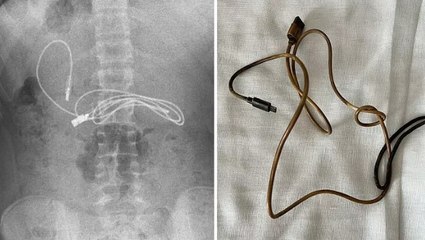

1 metrelik şarj kablosu ve toka! 15 yaşındaki çocuğun midesinden çıktı